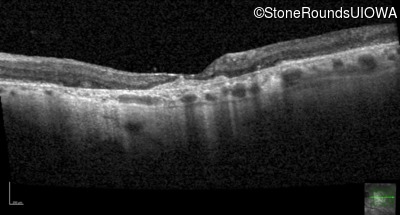

Optical Coherence Tomography - Left - 20/125

Exemplar / OCT Stack

OCT Stack